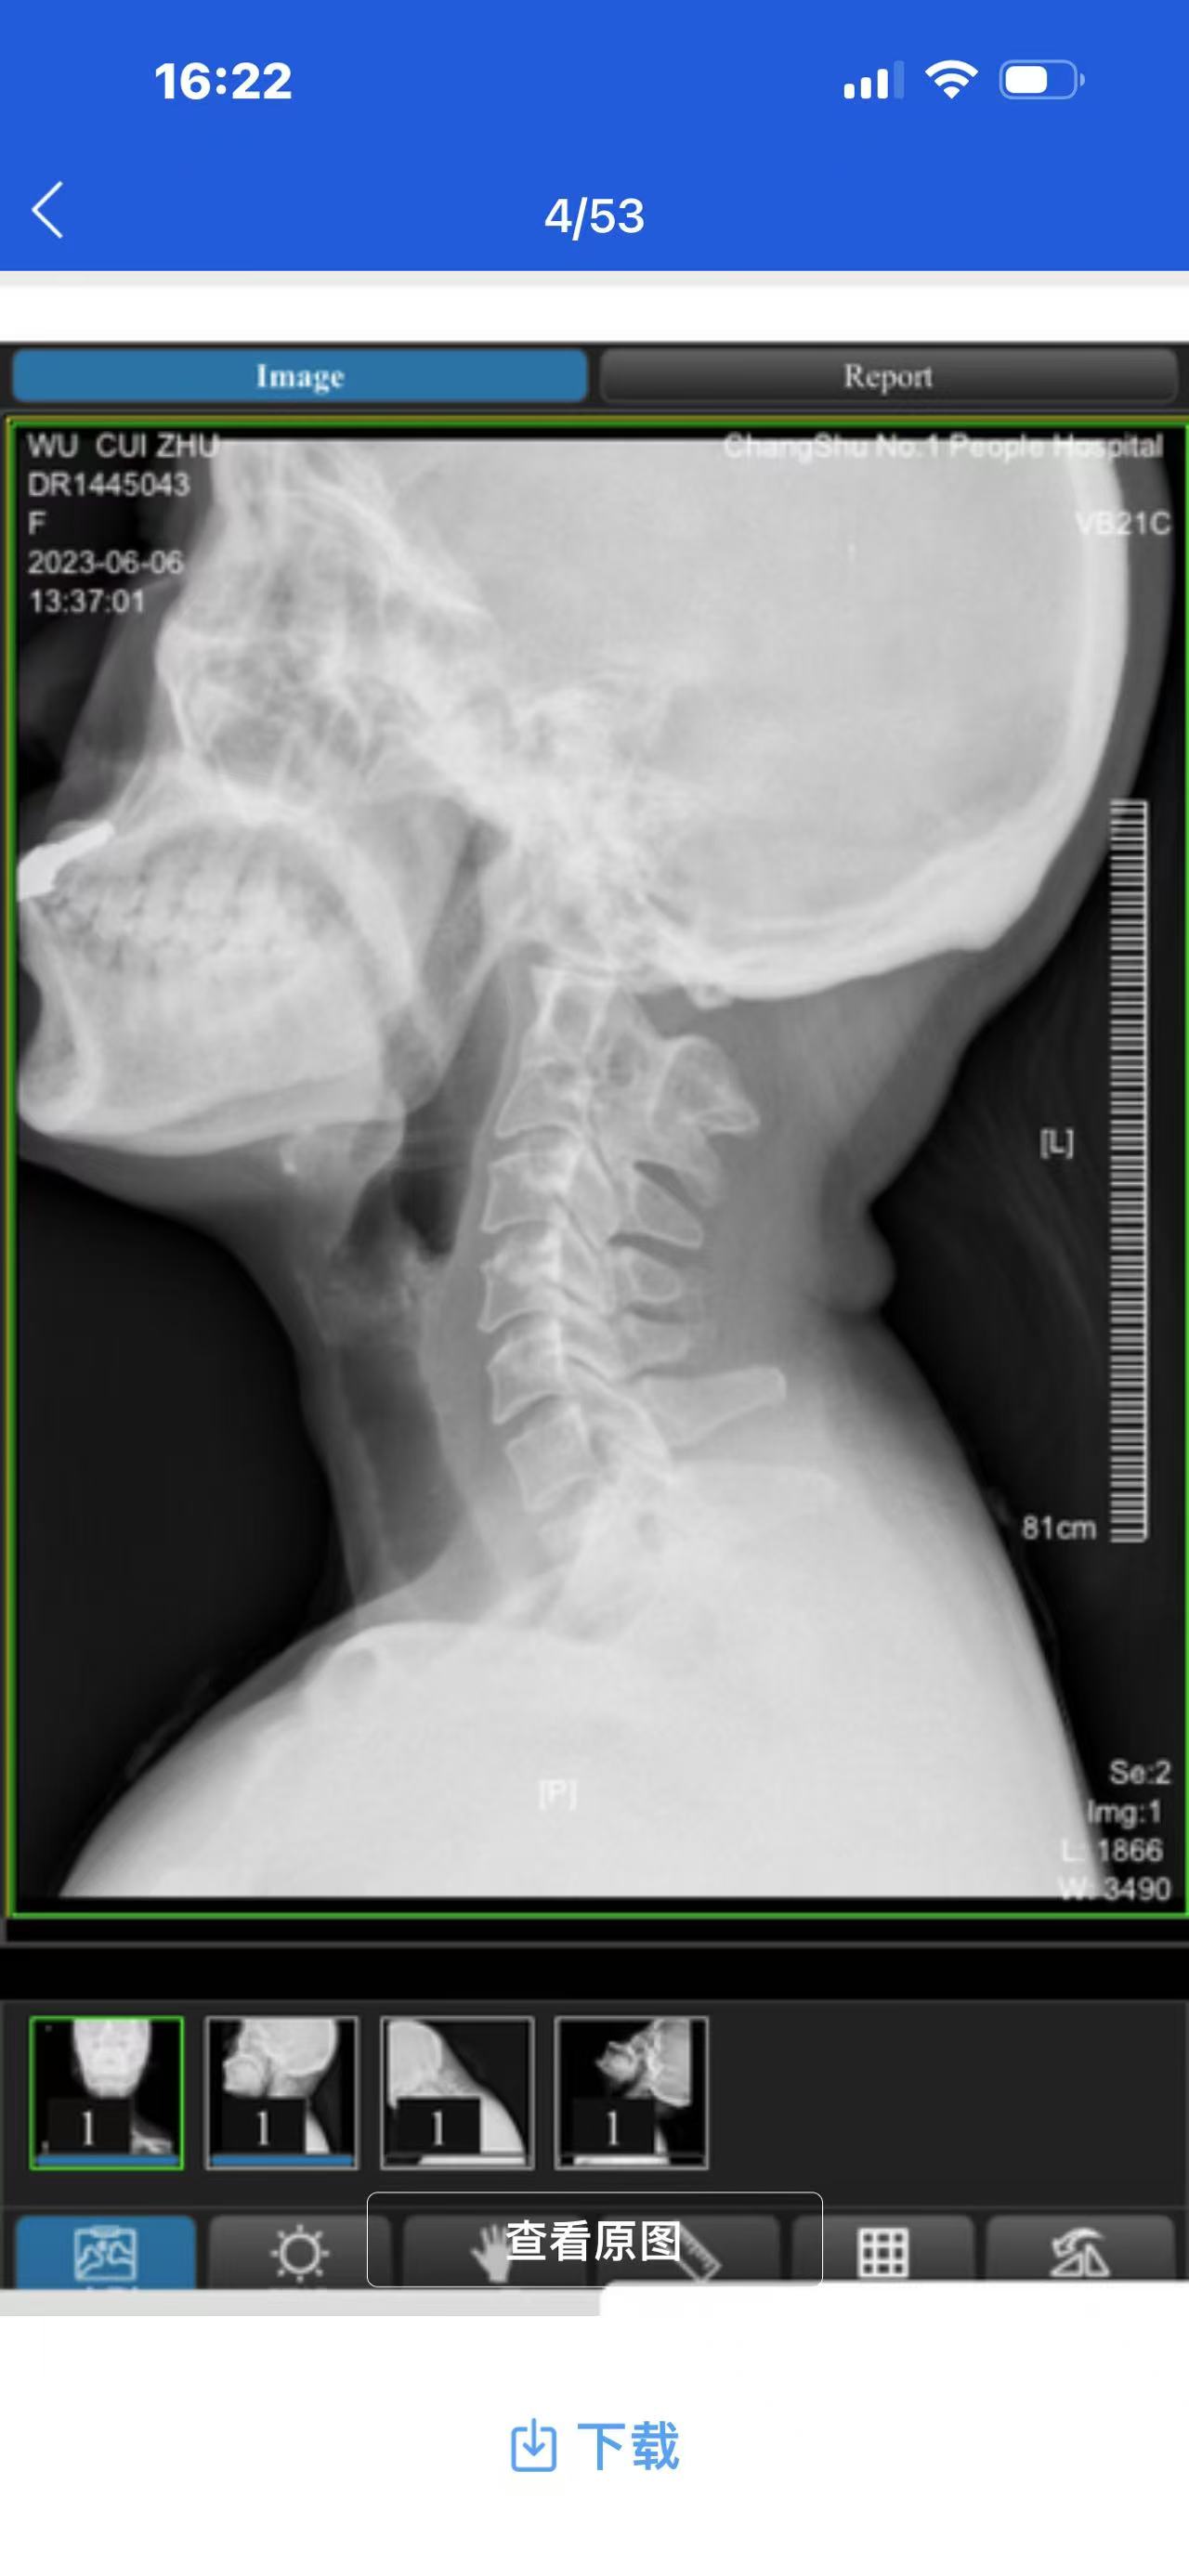

• 影像: